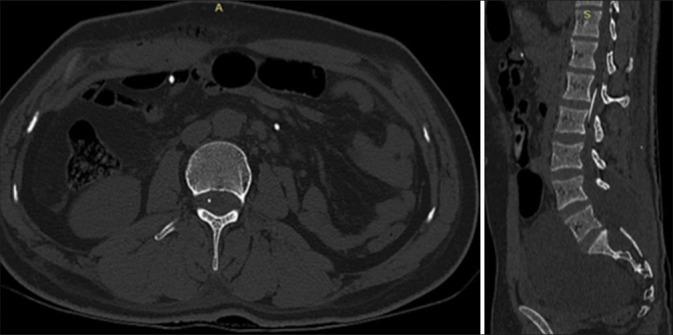

A 30-year-old male presented with a very large magnetic resonance-documented Tarlov cyst (Nabors Type 2) arising from bilateral S2 nerve root sheaths with marked pelvic extension. Although he was initially treated with a S1, S2 laminectomy, closure of the dural defect, and excision/marsupialization of the cyst, he later required placement of a thecoperitoneal shunt (TP shunt).

一名30岁男性,磁共振成像证实存在一个非常大的塔尔洛夫囊肿(纳伯斯2型),起源于双侧S2神经根鞘,并有明显的盆腔延伸。尽管他最初接受了S1、S2椎板切除术、硬脑膜缺损闭合以及囊肿切除/袋形缝合术,但后来仍需要放置脑脊膜腹膜分流管(TP分流管)。